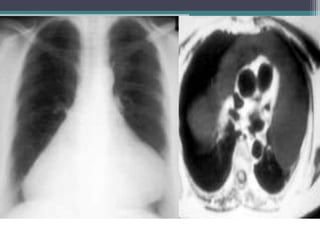

PA and lateral chest films show an

anterior mediastinal mass and a large

right pleural effusion.

Two contiguous slices

from an enhanced chest

CT exam show a

homogenous, solid,

anterior mediastinal mass

and a large right pleural

effusion.

Dx-Lymphoma, Non-

Hodgkin, Anterior

Mediastinal